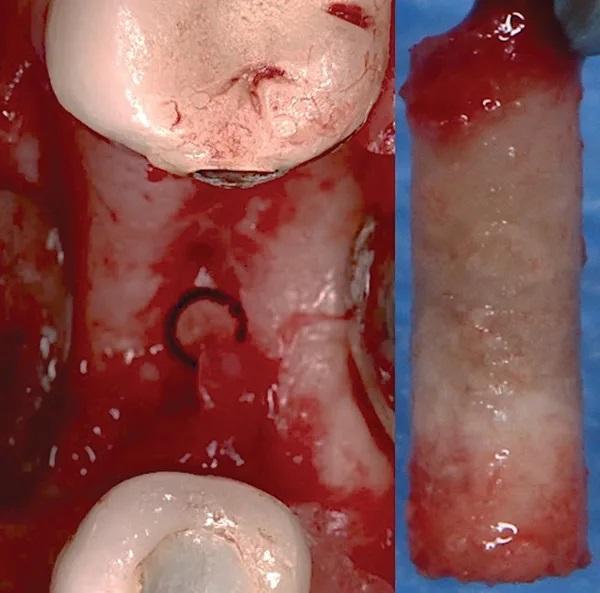

На 30-й неделе был получена костная стружка во время установки имплантата 4.5 зуба. Под местной анестезией повторно был выполнен крестообразный разрез лингвально, для увеличения ширины ороговевшей ткани и были отслоены полнотканные лоскуты с области щеки и языка.

Сначала при помощи остеотома диаметром 2 мм удалось получить костный блок размером 2 х 10 мм (фото 13). При клиническом осмотре в дистальной части нарощенного участка альвеолярного гребня была обнаружена грануляционная ткань, которая была удалена ручными инструментами. Трепанированный участок использовался в качестве начального этапа подготовки процедуре остеотомии имплантата при помощи которой было увеличен размер костного блока до 5 х 10 мм в соответствии с инструкциями производителя. Имплантат был помещен на 0,5 мм - 1 мм под надкостницу, была достигнута первичная стабильность (60 Нсм), и был установлен закрывающий винт. Проведено первичное закрытие раны.

Фото 13. Показан полученный костный блок размером 2 мм на 10 мм, который получили при использовании остеотома 2 мм.